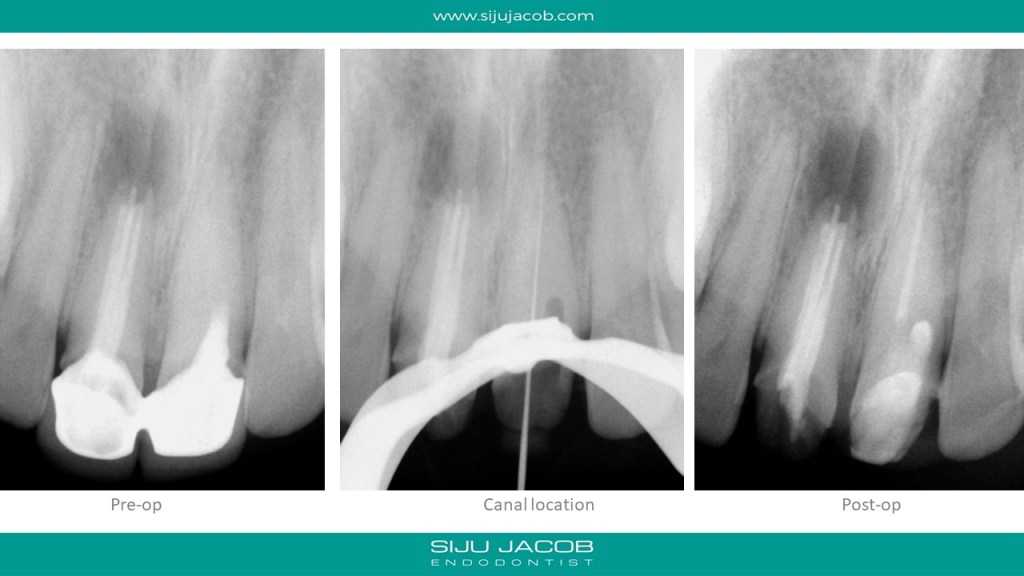

This was a patient who traveled from abroad from Treatment. We had only 9 days to do his treatment. So, we did endo and immediate surgery.